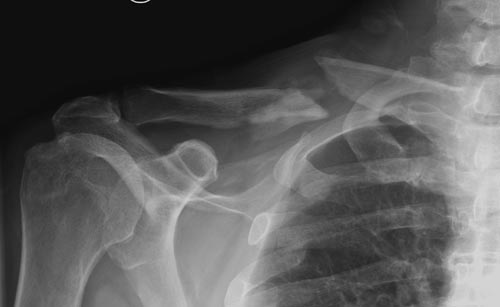

Уважаемые коллеги. Обратился пациент 29лет, оперирован в 2007 г. в Республиканском центре по поводу перелома ключицы и/м спицей, после несращения повторно оперирован в 2008 году, со слов больного освежение и повторно фиксация спицами, и обратился только через 6 лет, активные и пассивные движения в правом плечевом суставе в полном объеме, беспокоит только слабость при поднятии тяжести и подвижность в с/з ключицы. Р-снимок прилагается.Честно признаться, пока не знаю, что делать, имеются обычные пластины из ЦИТО, спицы, может, краевая резекция до появления «росы» дефект заполнить спонгиозной костью, фиксация и/м двумя спицами, загнуть оба конца спицы с компрессей, или пластина…или вообще не трогать. Прощу не критиковать, имеем то, что имеем, пациент в НИИТО не может ехать из-за финансов. С уважением Абдурашид.